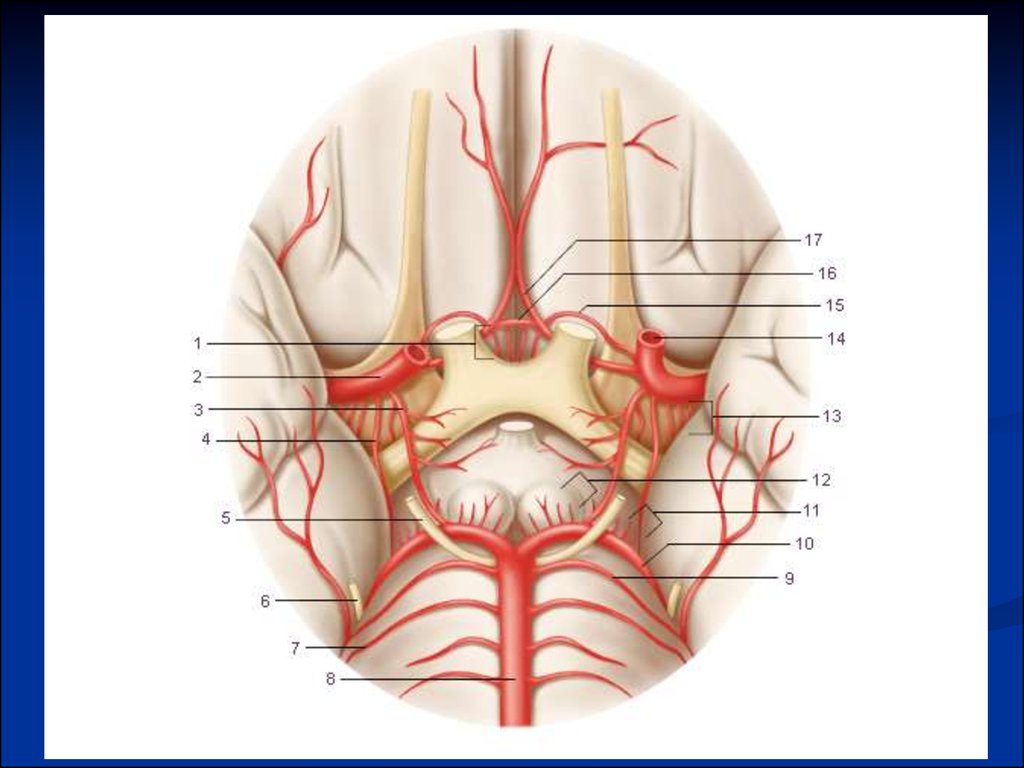

Анатомия: Задняя соединительная артерия мозга